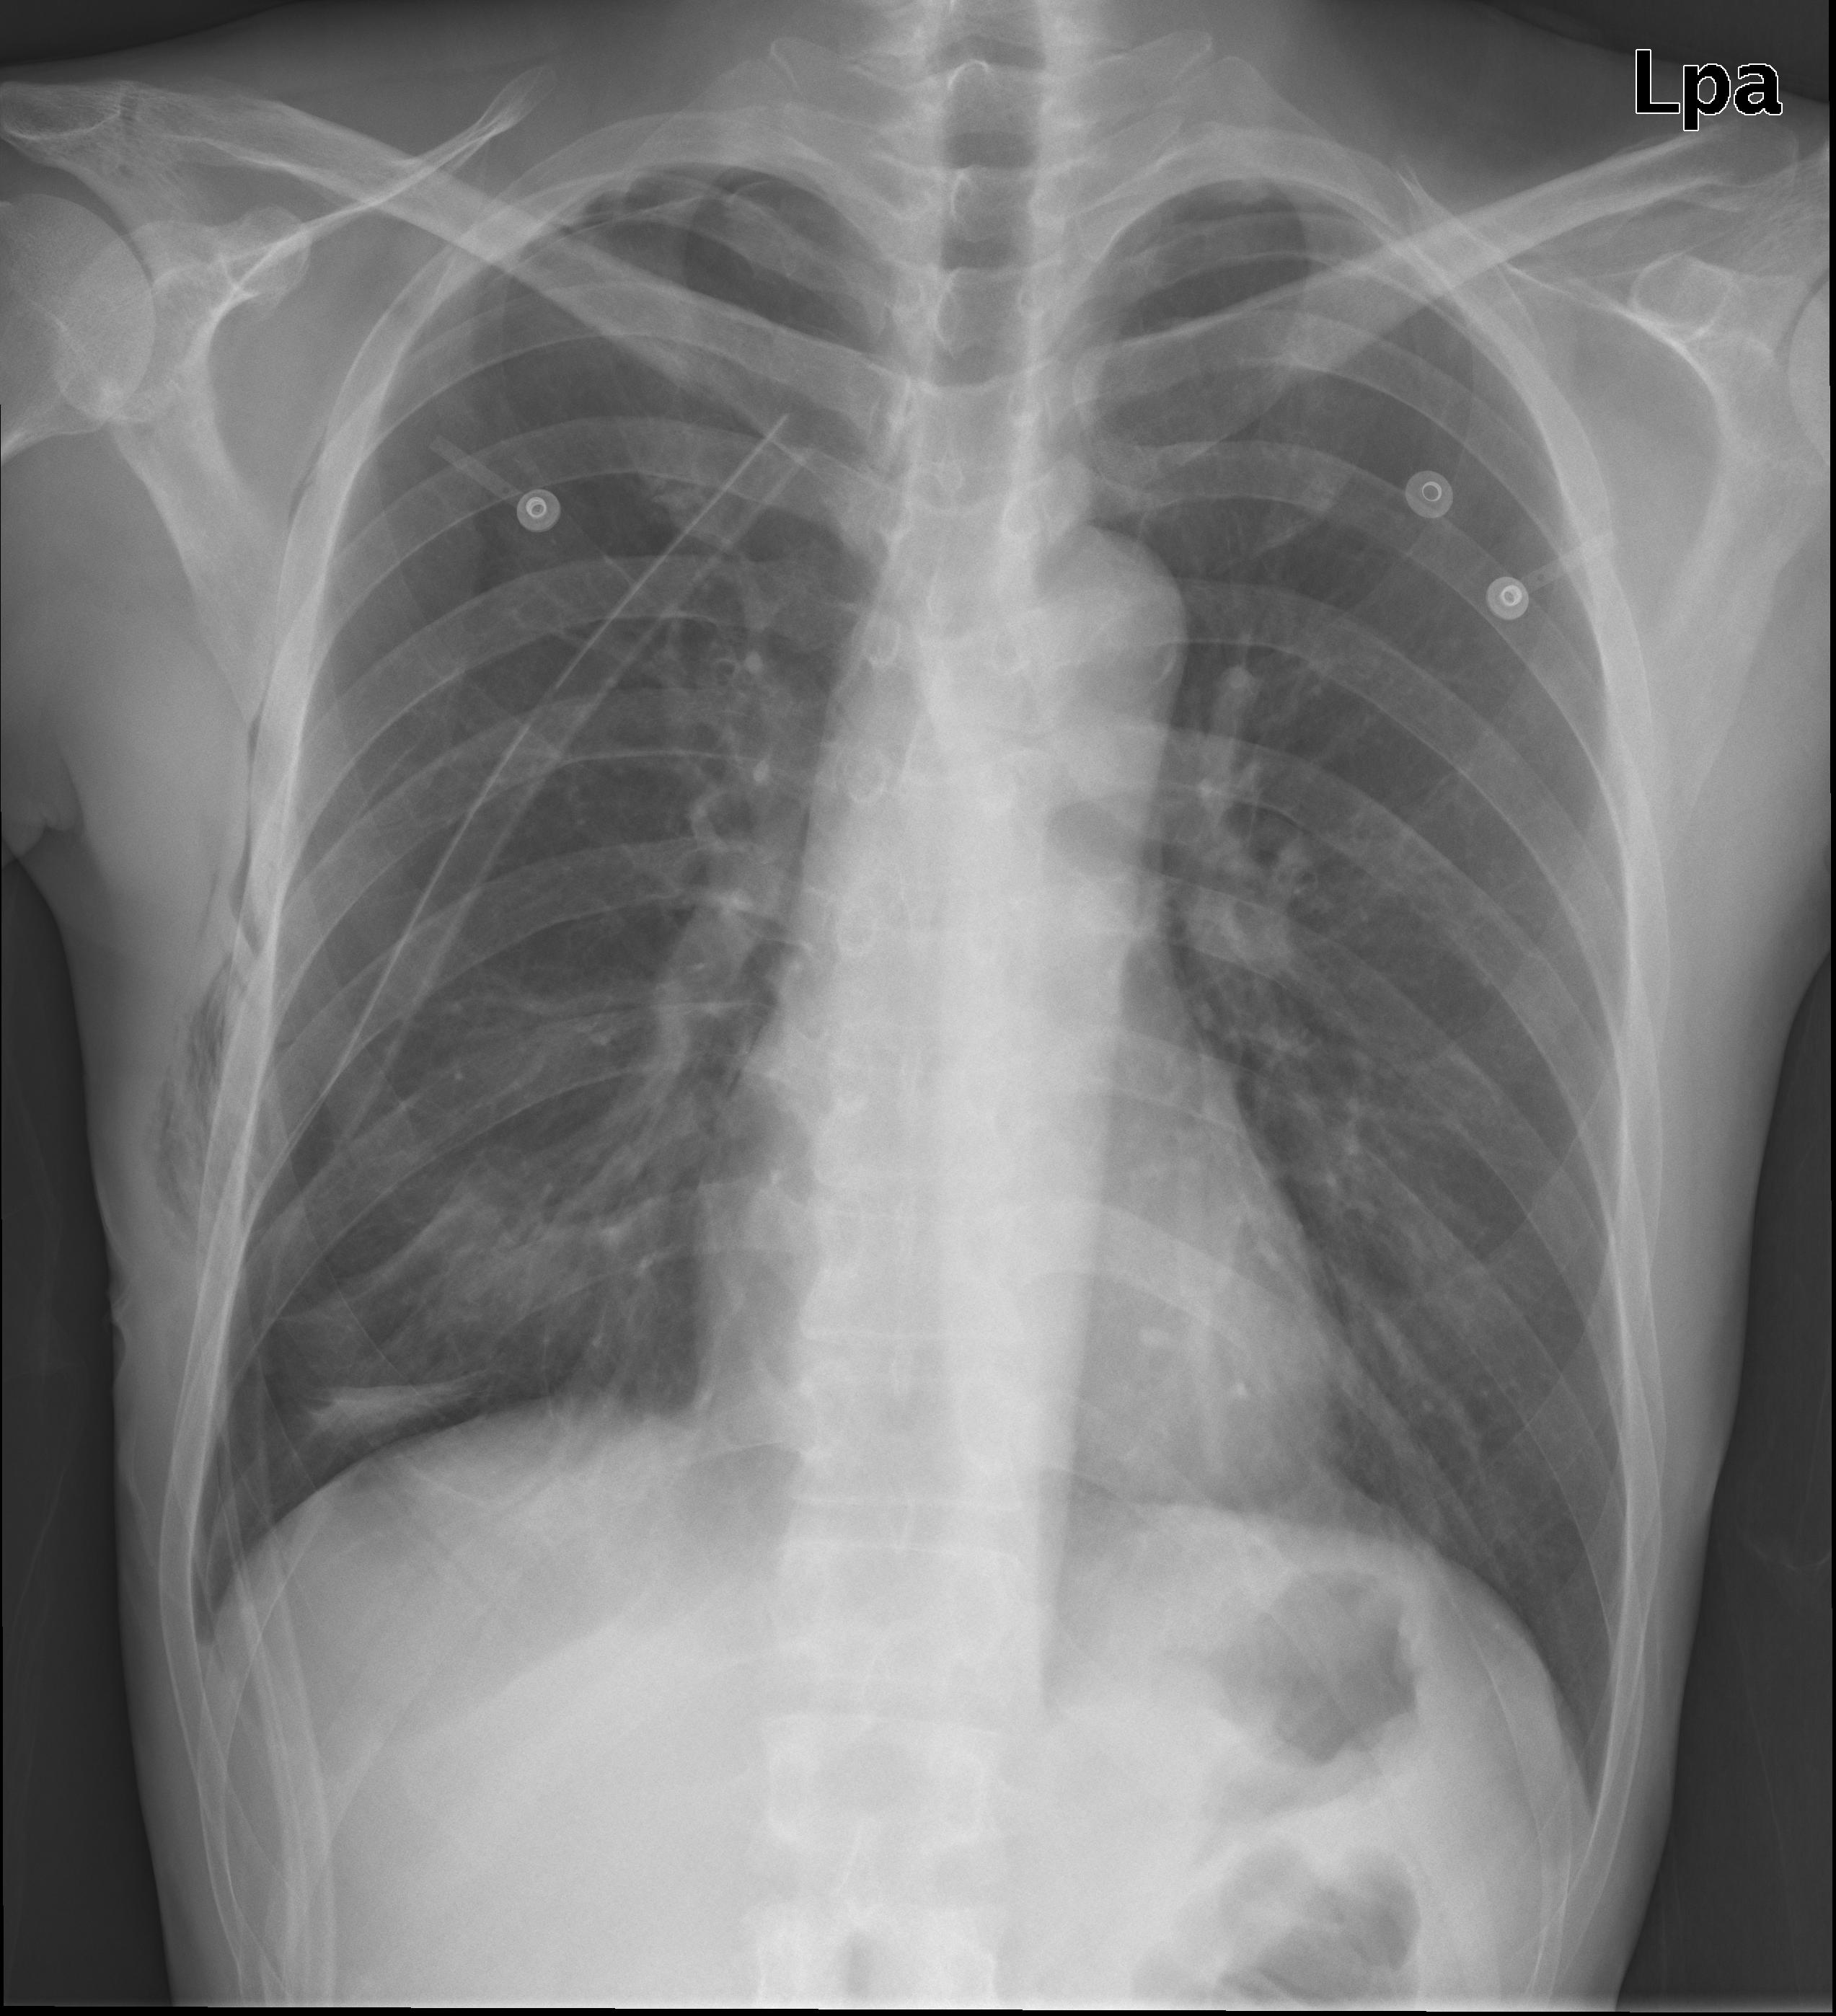

ABR(침대에서만 휴식명령을 어기고 돌아다니긴 했지만...대충 퇴원했다가/// 5일만에 다시 흉통이 와서...

기흉이 생겨서 박아넣은 CTD입니다.

완전 튜브 바람빠지는 소리처럼 크게 쓔욱 빠지더니 감쪽같이 10%의 통증으로 줄어들더군요.

해서 추석날 아침에 다시 입원.

그림의 우측은 정상적이 폐조직이고 좌측(원래는 오른쪽 폐)의 아래 검은 부분이 기흉의 흔적입니다.

가운데 기관지 옆의 튜브가 CTD튜브입니다.